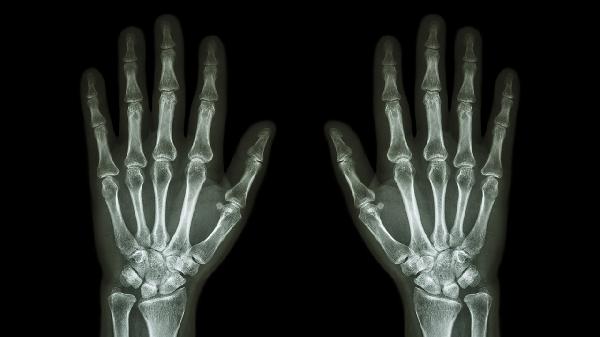

大拇指关节处出现包并伴有疼痛,可能与滑囊炎、腱鞘囊肿、关节炎等问题有关,建议及时到医院就诊以明确病因。具体治疗方法包括针对性的药物治疗、局部注射、手术治疗等,同时可通过热敷、减少活动等措施缓解症状。

滑囊炎是因为关节附近的滑液囊反复受压或摩擦引起的炎症,常导致关节处红肿、疼痛和包块。

腱鞘囊肿是一种常见的软组织肿块,通常由关节或腱鞘中过多的滑液积累引起,可能感觉柔软或稍硬,按压时可能引发疼痛。

关节炎可能由过度劳损、外伤或风湿免疫性疾病引起,从而导致关节出现肿胀、僵硬、疼痛。严重时,炎症可能导致关节处生成包块感。